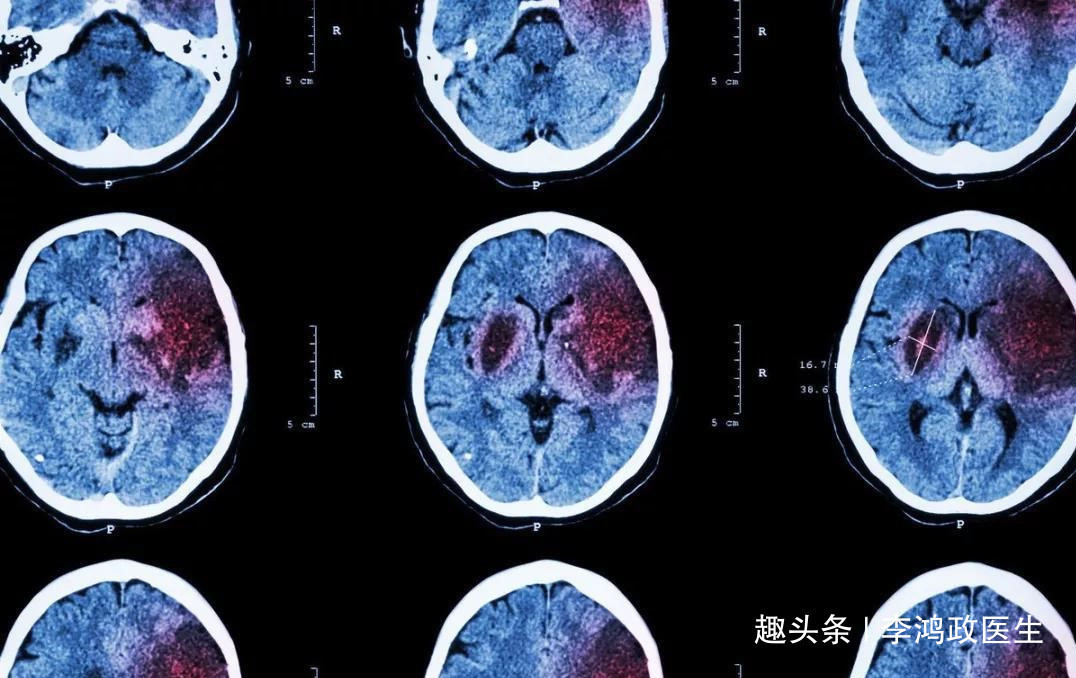

8、尿毒症昏迷?这个问病史很重要,患者既往有肾功能衰竭。或者抽血化验肝肾功能的时候发现血肌酐很高,高到爆表。都提示是尿毒症昏迷。9、肝昏迷?10、其他。太多了。文章一开头的那个女病人,迅速做了颅脑CT,是脑干出血。脑出血本来就很凶险,脑干出血更加是凶险中的凶险,因为人体的呼吸、心跳中枢都在脑干那里,一旦脑干出血,这些中枢都可能受到影响。患者会迅速致死。经过询问病史,患者有高血压数年,一直不吃药,试图靠喝茶来降低血压,哎呀,真是愚蠢啊。如果喝茶能有效降低血压,那该多好。